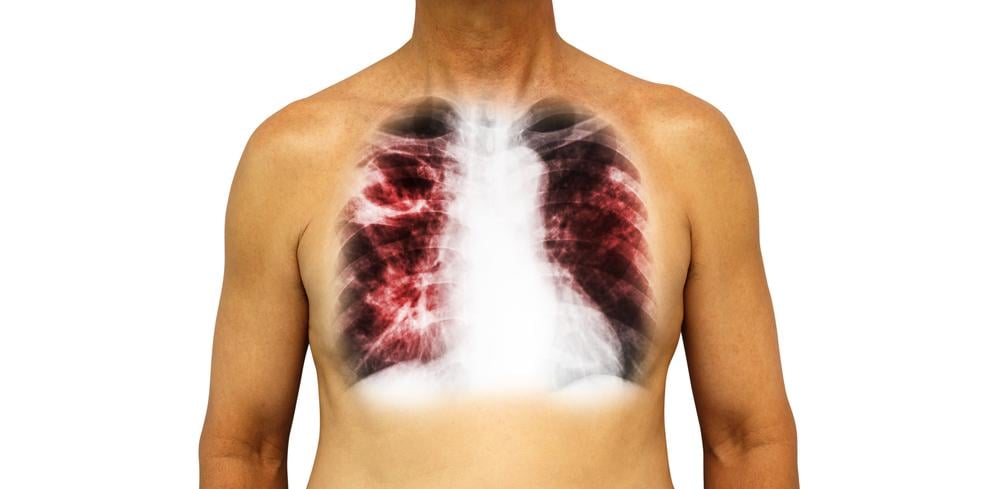

Viêm phổi kẽ (VPK – interstitial pneumonia) là một nhóm bệnh lý thuộc bệnh phổi kẽ (hay còn gọi là bệnh phổi nhu mô lan tỏa), là tình trạng viêm ở khoảng kẽ (khoảng trống giữa các phế nang và các mạch máu xung quanh chúng).

Sau đó, bác sĩ sẽ chỉ định thực hiện các kỹ thuật cận lâm sàng như xét nghiệm chức năng phổi, chụp X-quang ngực, siêu âm tim, chụp cắt lớp vi tính, xét nghiệm bệnh tự miễn, xét nghiệm vi sinh, xét nghiệm máu, nội soi phế quản, sinh thiết phổi để tìm ra nguyên nhân và chẩn đoán chính xác nhất.